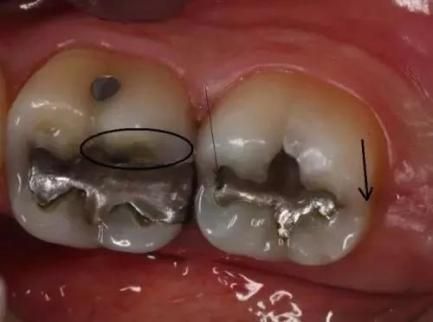

牙隐裂

冰毒会使服用者感到焦虑、亢奋或紧张 , 从而导致磨牙 。 你能看到他们的牙齿上有明显的磨耗痕迹 。 有时候就算是吃一些很软的食物(如土豆泥) , 也会使服用者的牙齿出现隐裂 。

龋齿

冰毒成瘾者会因为口干反应而渴望吃含糖量高的食物和饮品 。 这样 , 口腔内靠糖类为生的细菌会大量繁殖 , 并分泌酸性物质 , 使牙齿损坏更严重 。 冰毒服用者的龋齿通常会从牙龈边缘发展到整个牙齿 , 前牙首当其冲 。